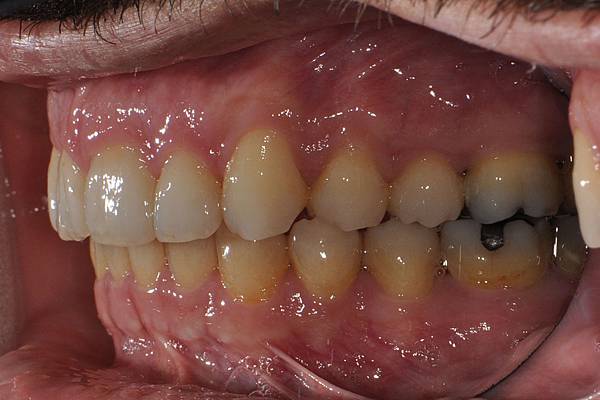

台灣的牙科醫療品質, 連外國人都說讚!此案例為深咬合併二級咬合 林醫師藉由正中上顎骨釘(HPPG technique)做上顎全齒列後移改善暴牙 讓本來五官就相當立體的艾先生,笑起來更燦爛了! 治療前/治療後-以上案例由林昇進醫師提供 分享到